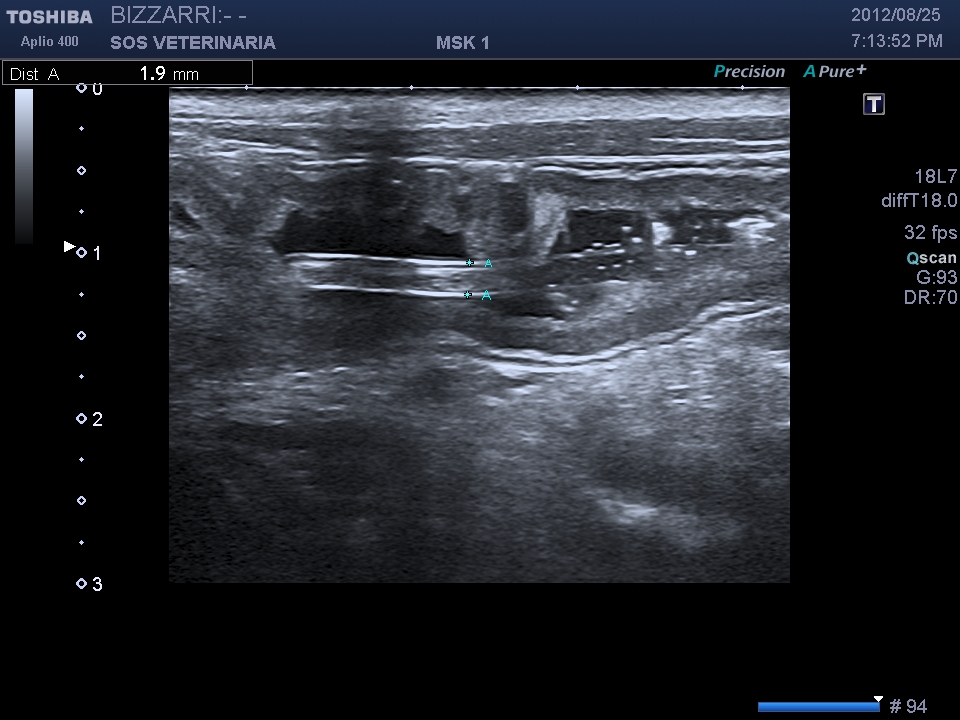

ascaride all’interno del lume diametro inferiore ai 2mm,non si evidenzia cono d’ombra

L’ascaride si differenzia ecograficamente dal copo estraneo filiforme per la presenza della parete esterna (cuticola) ,una parte interna parenchimale e l’assenza di cono d’ombra ,inoltre l’intestino puo’ essere spastico ma mai circonvoluto con pattern a fisarmonica.